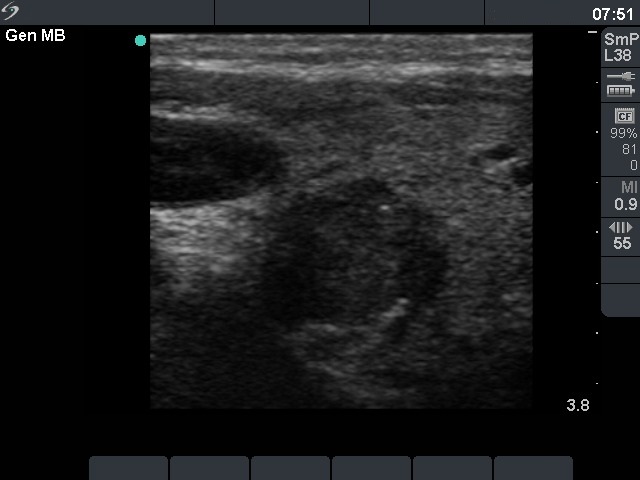

Ultrasonography. The right lobe was intact, while there was a hypoechogenic nodule in the left lobe. The lesion had hyperechogenic areas and coarse calcifications. A lymph node was detected lateral to the left thyroid.